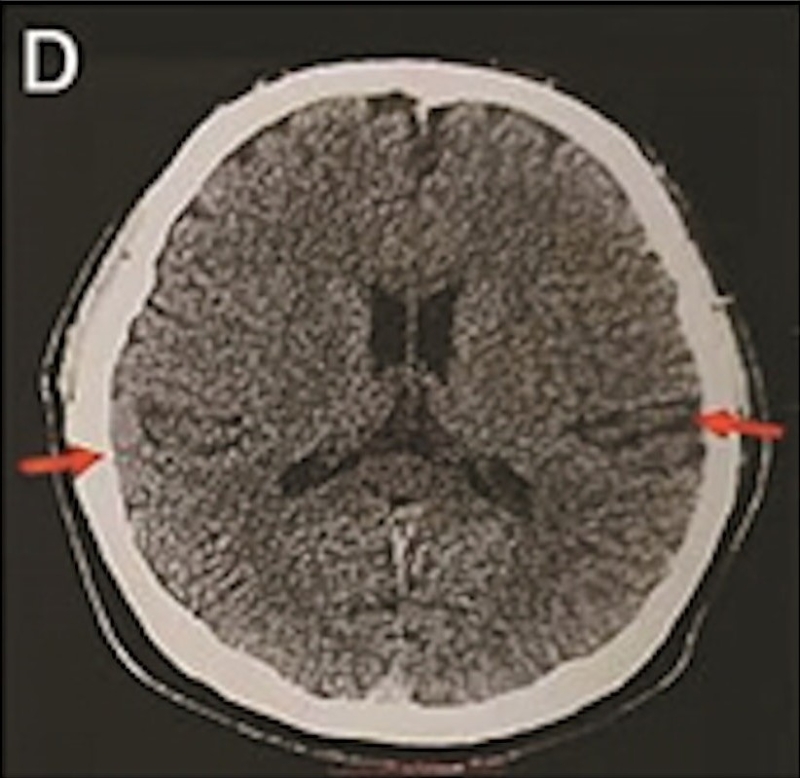

最年輕的19歲阿茲海默癥男子腦部掃描結(jié)果:

▲19歲阿茲海默癥(認知障礙癥/腦退化癥)男子腦部掃描結(jié)果。北京青年報

該名19歲男子到醫(yī)院接受多項檢查,包括腦脊液指標檢測及正電子掃描。結(jié)果顯示,他出現(xiàn)輕度腦萎縮等癥狀,最終被臨床診斷為“阿茲海默癥”。